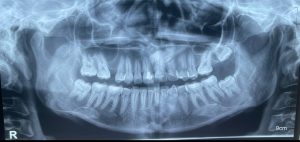

Tratamientos Ortodoncia Blanqueamiento dental Zoom Contacto 72 2795 9597 Marcar Ahora Envia whatsapp Visita nuestro facebook